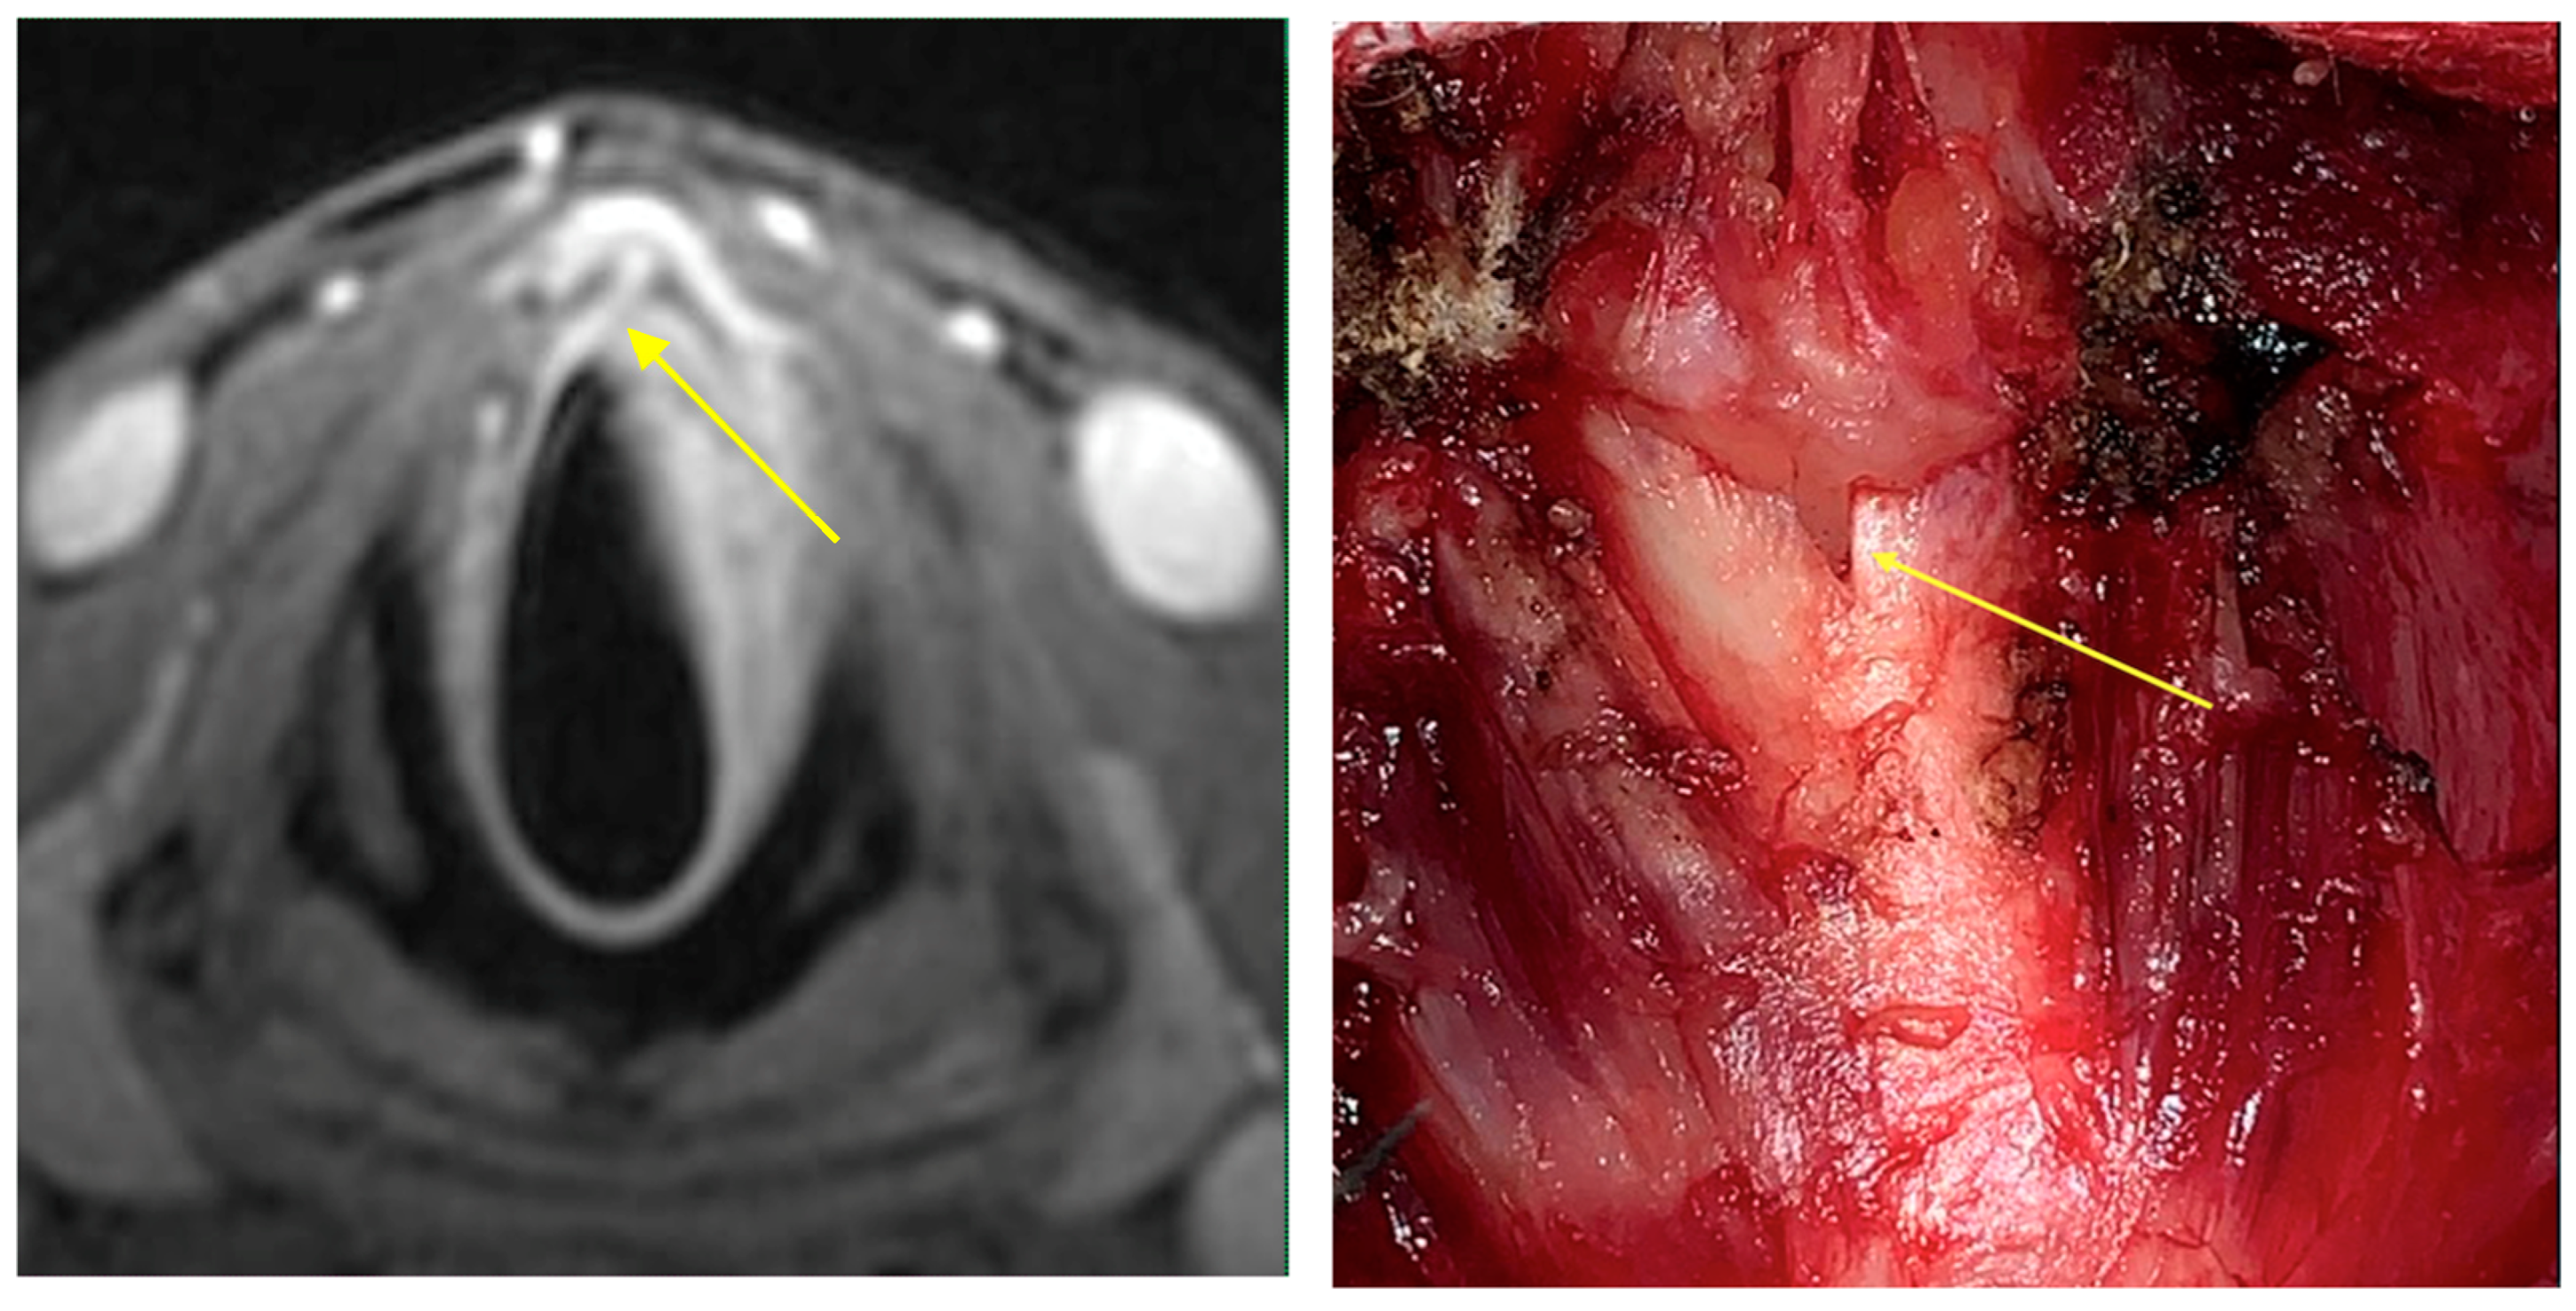

Intraoperative endoscopy allowed for a thorough reassessment of the tumor extension and highlighted some clinical-endoscopic elements of suspected initial extra laryngeal extension (Figure 1 and Figure 2).

Figure 1. Glottic squamous cell carcinoma cT3 (left vocal cord): endoscopic and radiological (MRI) picture: the tumor was likely to be sub-staged with endoscopic evaluation alone.